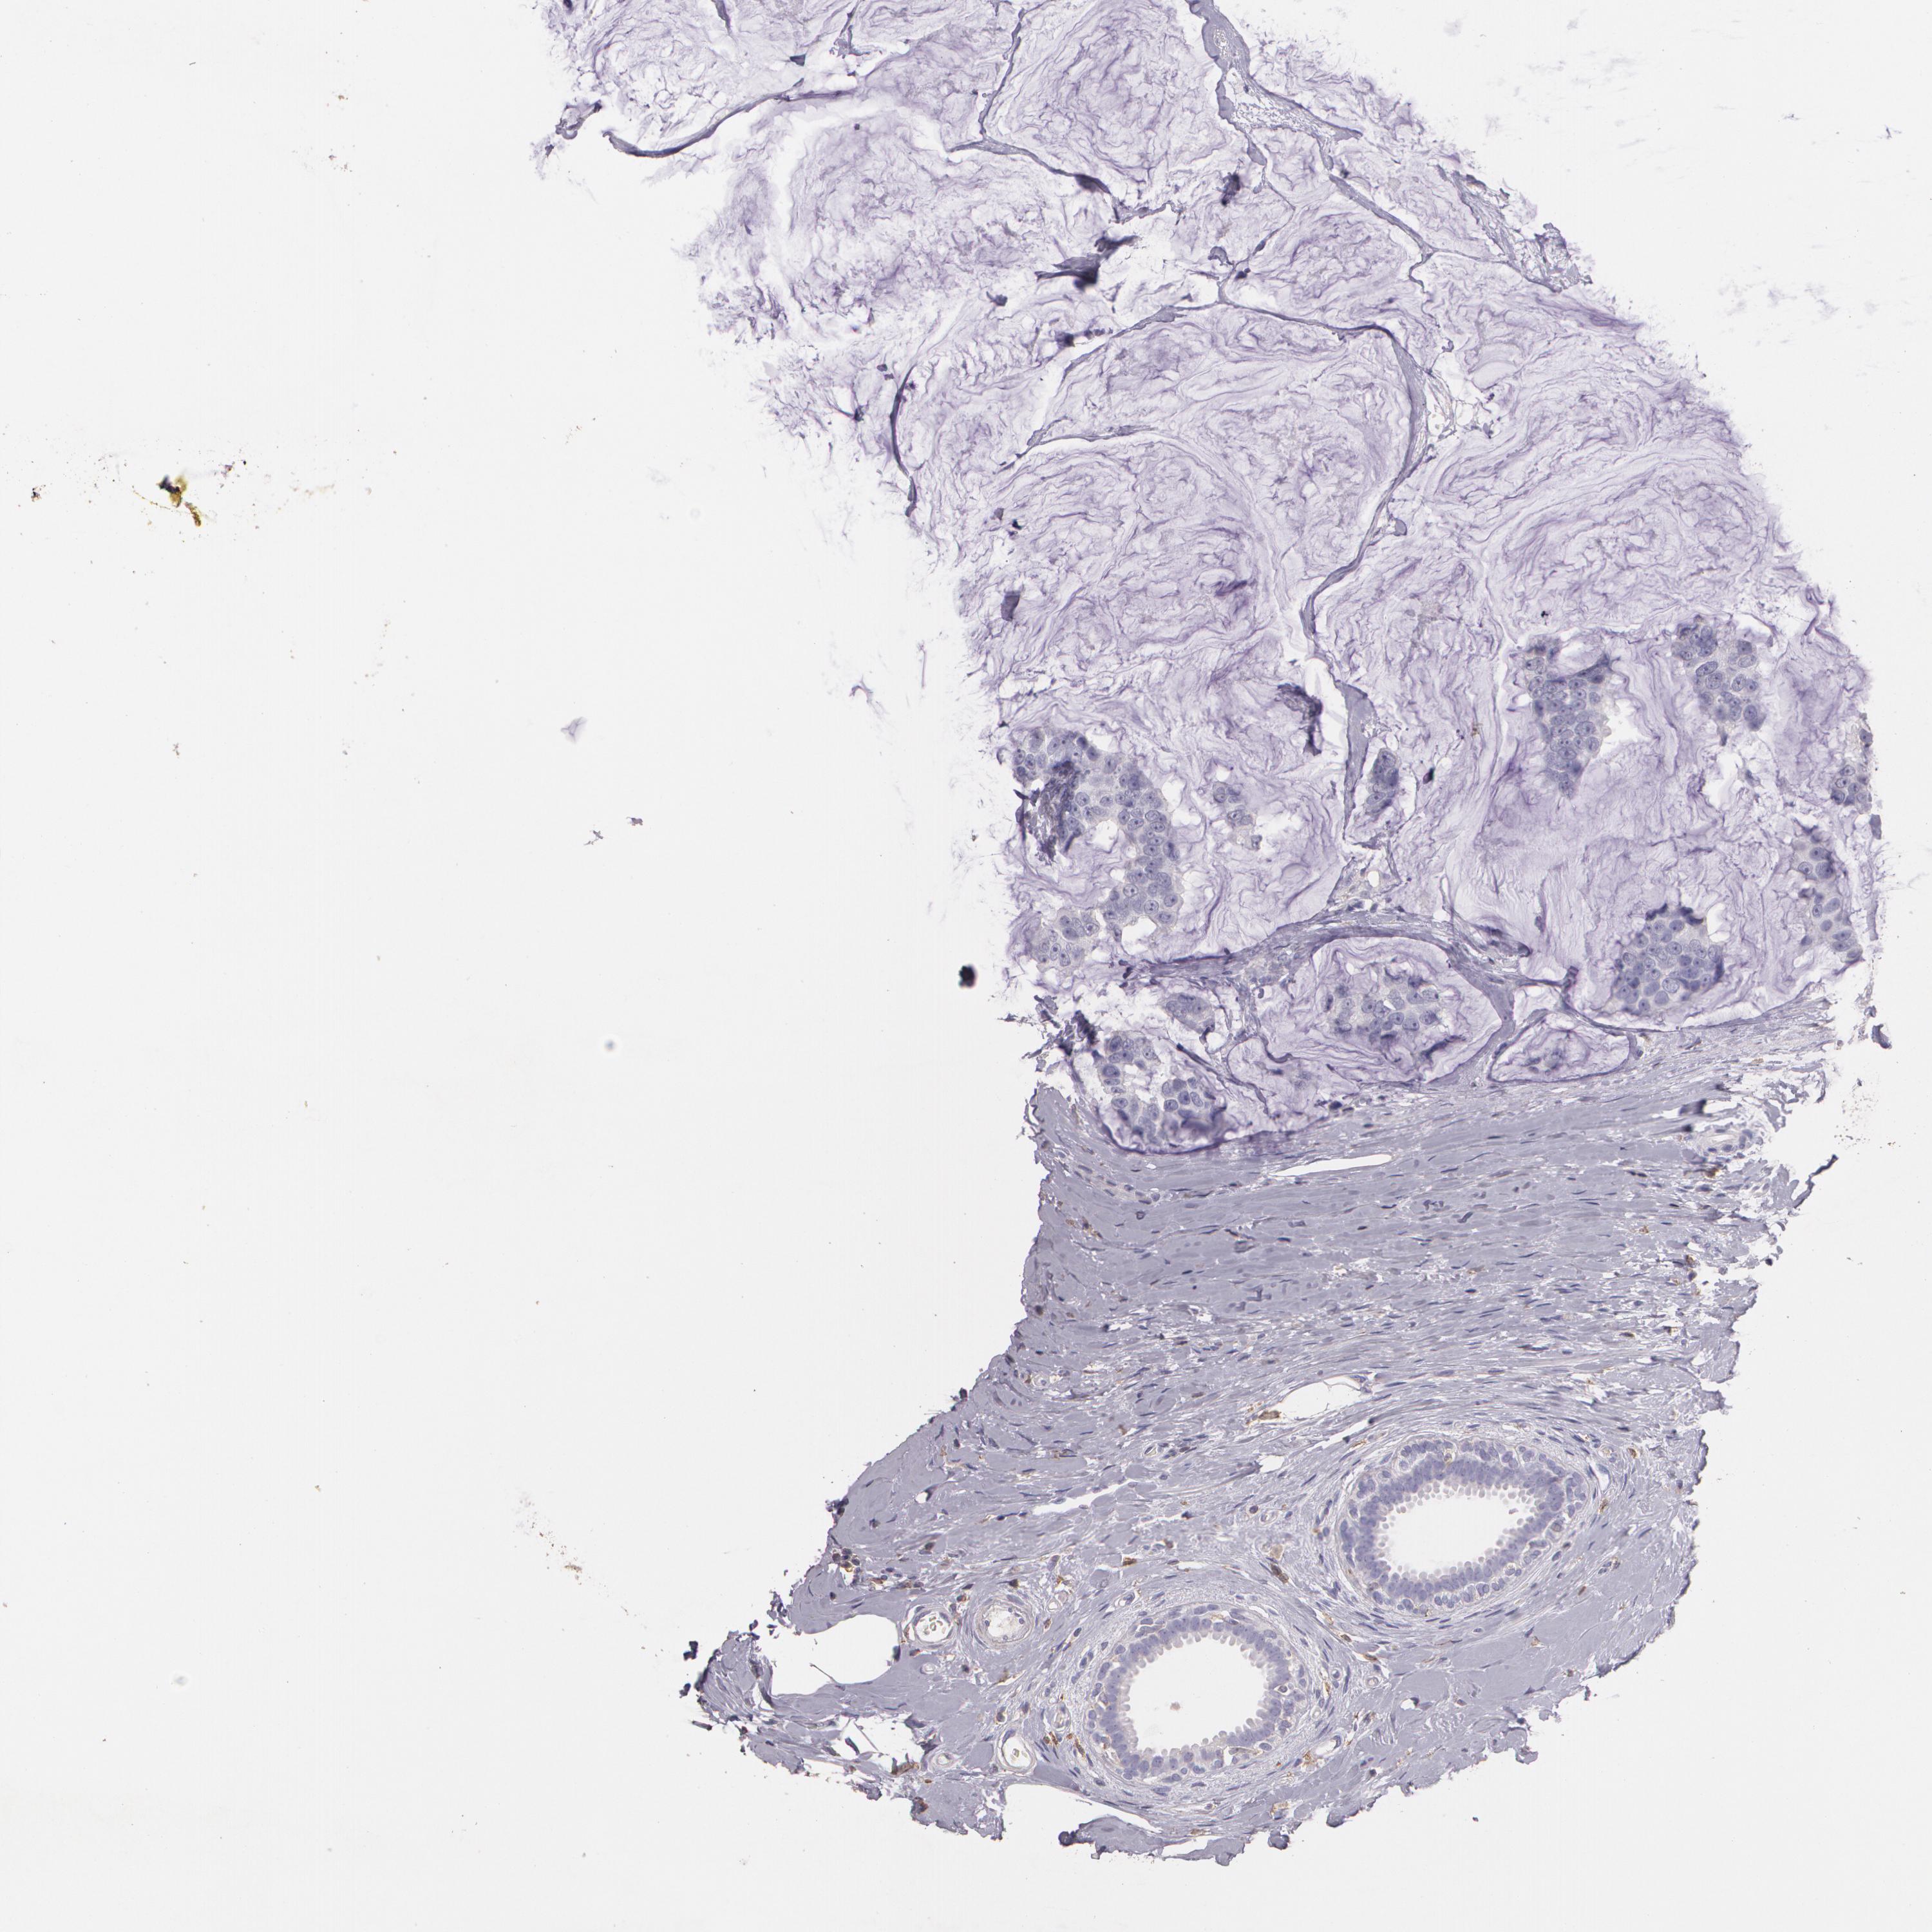

Breast cancer

Human cancer